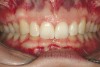

Figure 2e  Teeth Nos. 5 and 12 were converted to Nos. 6 and 11, and Nos. 6 and 11 were converted to Nos. 7 and 10. Nos. 4 and 13 were enlarged. Note stability and absence of orthodontic relapse. Before-and-after smiles.

Figure 2e

Figure 2f  Teeth Nos. 5 and 12 were converted to Nos. 6 and 11, and Nos. 6 and 11 were converted to Nos. 7 and 10. Nos. 4 and 13 were enlarged. Note stability and absence of orthodontic relapse. Before-and-after smiles.

Figure 2f

Figure 2g  Periodontist: Edward P. Allen, DDS, PhD. Prosthodontist: Robert R. Winter, DDS.

Figure 2g